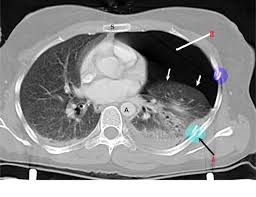

A Classification Of Pulmonary Nodules By Ct Scan Ecancer

A Classification Of Pulmonary Nodules By Ct Scan Ecancer from ecancer.org